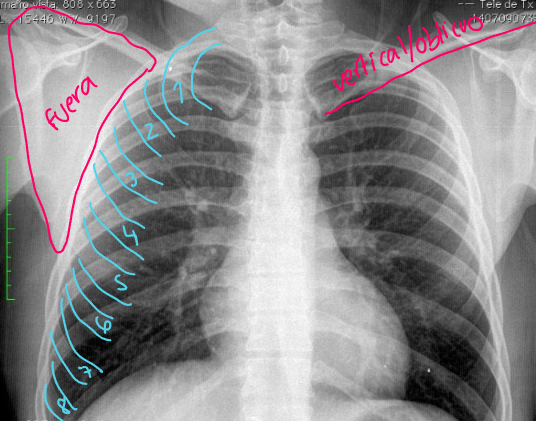

¿Qué distribución tiene la lx?

"Alas de mariposa"

Distribución en "alas de mariposa" se asocia a:

Influenza | O edema pulmonar alveolar